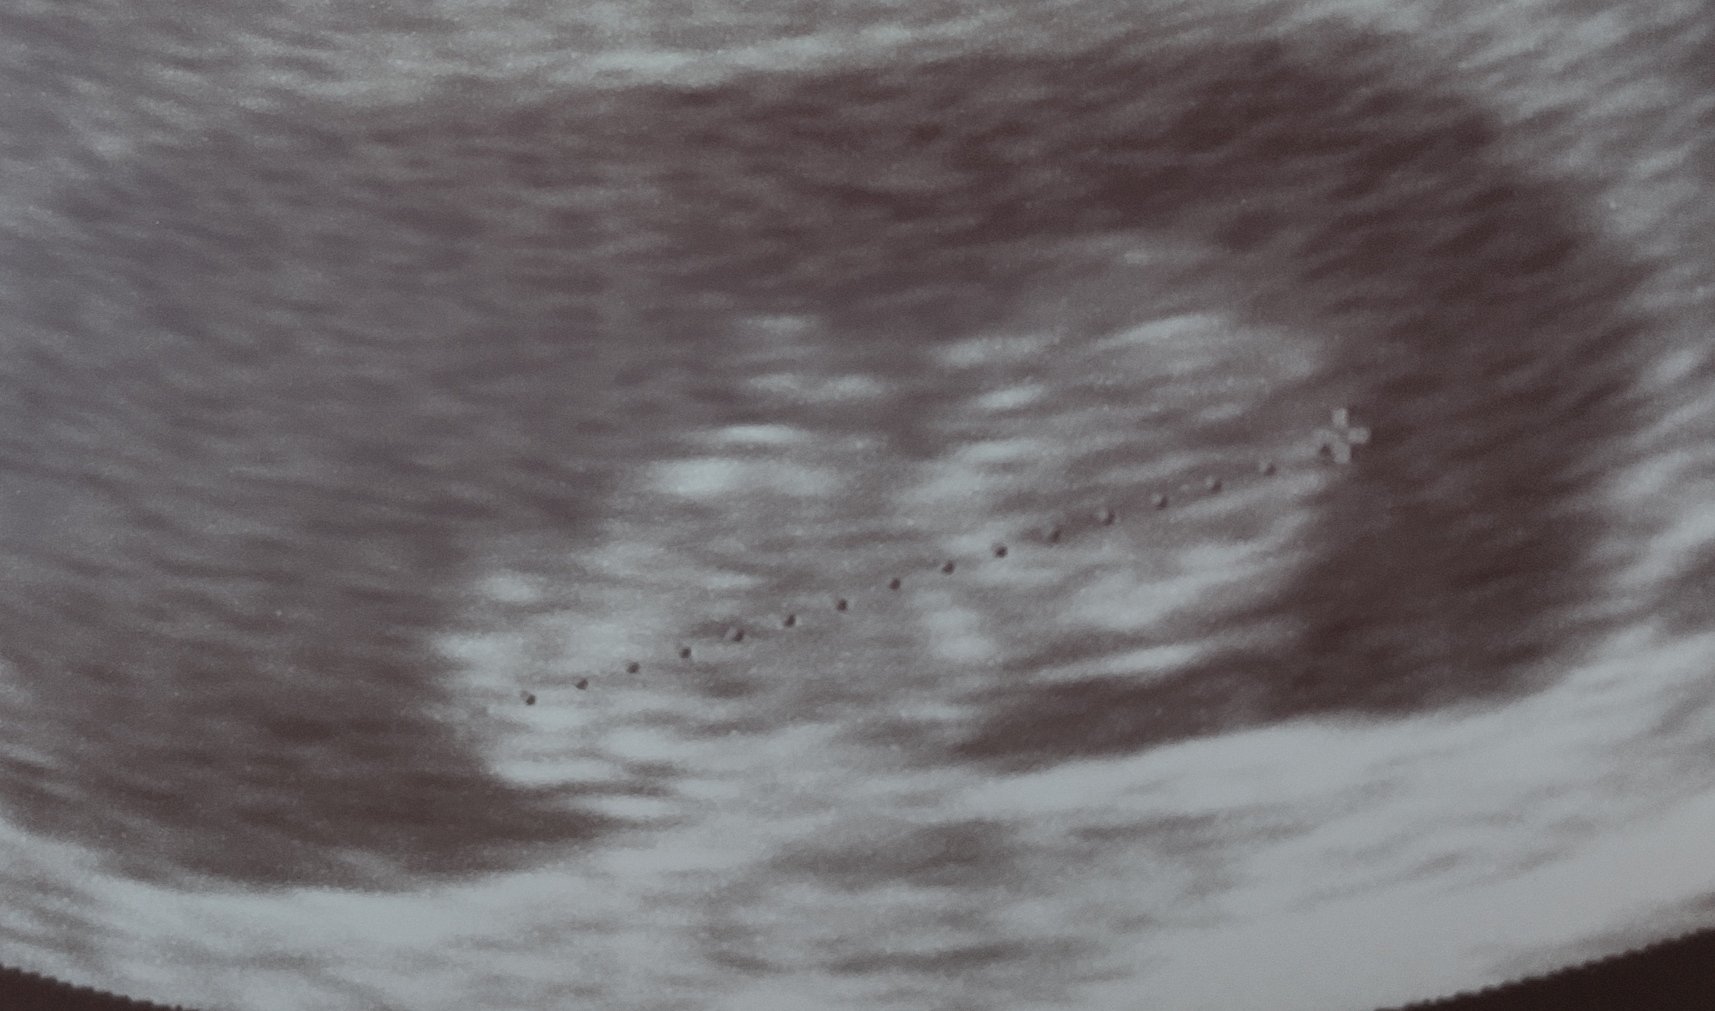

Момичета, идвам най-после да ви наръся щедро и обилно с много шавлив все още неопределен прашец! Днес бях на преглед и човечето си расте, за първи път го видях като оформено бебе и за първи път го видях да мърда. Заслужава си всичко, през което преминаваме, за да ги има нашите бебета! След двете БХ още ми се струва нереално, че го виждам съвсем истинско и охранено да ми маха с ръчички. Прегръдки на всички, не спирам да ви чета! 🍀🍀🍀